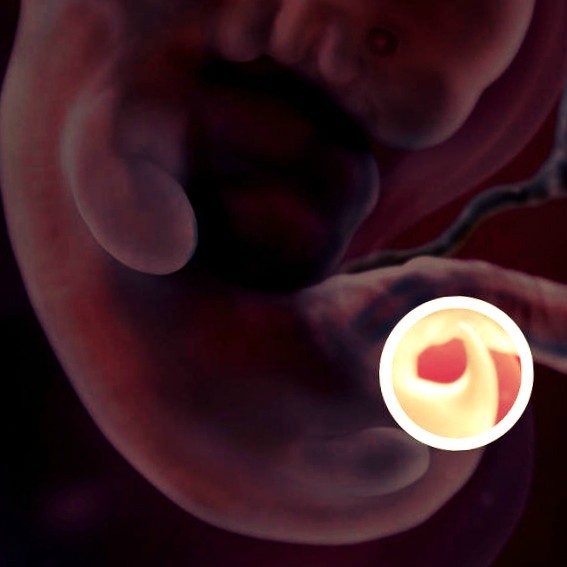

На этой неделе у малыша появляются пальчики, а также он теперь может сгибать ручки в локтях и запястьях. Появляется пигментация радужки, формируются половые органы, хотя на этом этапе еще нельзя определить, будет ли у вас мальчик или девочка. Но если любопытство не дает покоя, попробуйте отгадать пол ребенка с помощью нашего теста. Меняются не только внешние черты, но и внутренние органы. Формируется кишечник, который пока расположился в пуповине, потому что в брюшной полости малыша еще недостаточно места. Даже на такой ранней стадии своего развития кишечник выполяет свою функцию, выводя продукты жизнедеятельности плода из организма. Через месяц, когда в животе малыша станет попросторнее, кишечник окажется в брюшной полости.

Через 3 недели после зачатия образуется желточный мешок.

Он производит кровяные клетки, пока эмбрион не научился делать это сам.